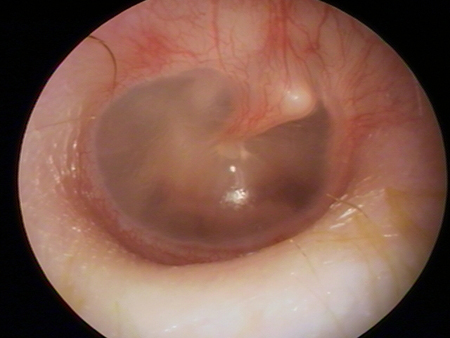

On otoscopy the tympanic membrane will appear opaque, bulging, and inflamed with erythema, and there will be a purulent middle ear effusion. If there is a tympanic membrane perforation, purulent otorrhoea will be seen.[Figure caption and citation for the preceding image starts]: Otoscopy appearance of a bulging, erythematous tympanic membrane and absent landmarksFrom the personal collection of Dr Armengol [Citation ends].